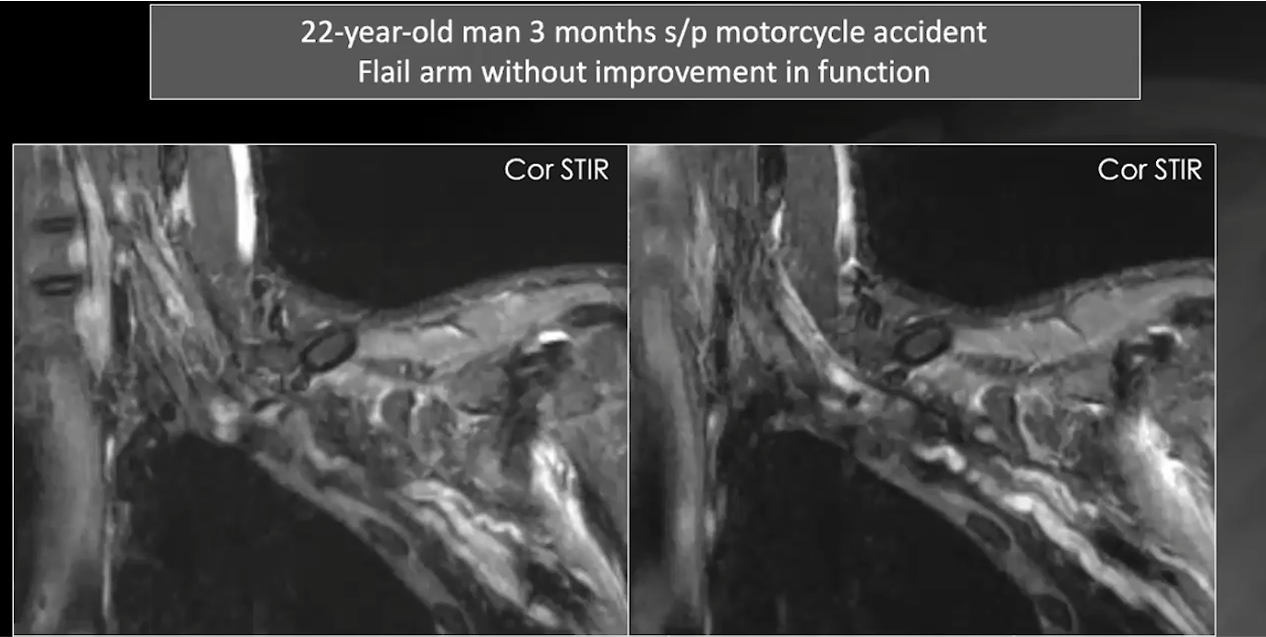

post ganglionic neuropraxia

complete transection and redundancy of the divisions

partial disruption of the nerve which scarred and turned into a neuroma